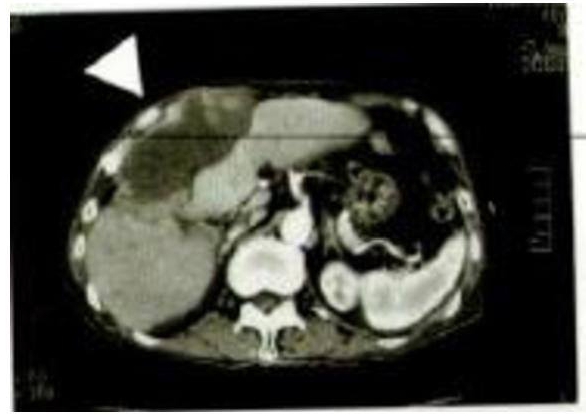

Imaginea CT stânga aparține unui pacient de sex masculin, în

vârstă de 81 ani, suferind de carcinom hepatocelular.

La stânga sus, porțiunea mai întunecată (simbolul ) decât perimetrul adiacent reprezintă zona afectată de cancer. Mărimea este considerabilă, de 102 mm x 44 mm, stadiul clinic fiind 4 (starea cea mai avansată).

Vârsta și stadiul bolii au determinat renunțarea la tratament, a luat însă parte la un studiu referitor la eficacitatea Oyama Agaricus, cu inițierea ingerării ciupercii menționate.